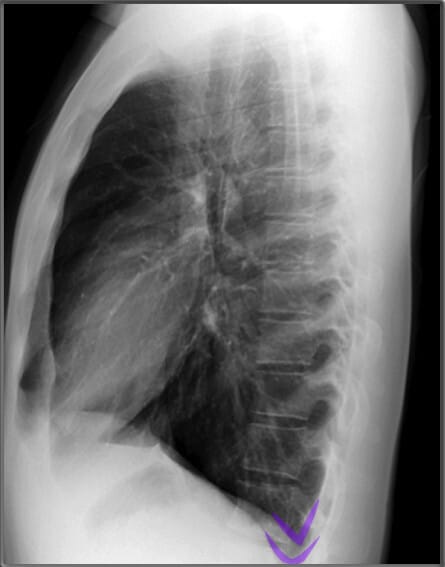

Lateral View of Chest X-ray

측면 영상은 폐, 심장 및 척추의 깊이를 평가하는 데 유용합니다.

| 흉골 (Sternum) |

| ✅ 측면 영상에서 길게 보이며, 정상적으로는 매끄럽고 연속적인 윤곽을 보여야 합니다. 골절이 있는 경우 불연속적인 선이 관찰될 수 있습니다. |

| 우심실 (Right Ventricle) |

| ✅ 심장의 전방 부분을 차지하며, 비대해지면 폐고혈압을 고려할 수 있습니다. |

| 좌심방 (Left Atrium) |

| ✅ 좌심방은 측면 영상에서 심장 후방에 위치하며, 기관(trachea) 바로 앞쪽에 위치합니다. 좌심방이 확장되면 기관이 뒤로 밀리는 소견이 나타날 수 있습니다. |

| 좌심실 (Left Ventricle) |

| ✅ 좌심실은 심장의 가장 하부와 후방을 차지하며, 비대해지면 좌측 횡격막과의 경계가 불명확해질 수 있습니다. |

| 척추체 (Vertebral Bodies) |

| ✅ 척추체는 정상적으로 크기와 모양이 균일해야 하며, 압박 골절이나 골 용해 소견이 있으면 병적 상태를 고려해야 합니다. |

| 추궁근 (Pedicles) |

| ✅ 추궁근은 척추의 일부로, 좌우 대칭적으로 나타나야 합니다. 종양이나 감염으로 인해 변형되거나 소실될 경우 병리적 상태를 의심할 수 있습니다. |

하늘색이 Vertebral bodies, 파란색 (코발트 블루)가 Pedicles| 기관 (Trachea) |

| ✅ 흉부 중앙에서 공기가 가득 찬 검은 색의 관 형태로 보이며, 정상적으로는 앞쪽으로 약간 기울어져 있습니다. 협착되거나 편위된 경우 기도 병변을 의심할 수 있습니다. |

| 늑골횡격막각 (Costophrenic Angle) |

| ✅ 늑골과 횡격막이 만나는 각도로, 정상적으로 뚜렷하고 예리하게 보여야 합니다. 둔해지거나 소실되면 흉수(pleural effusion) 가능성을 시사합니다. |